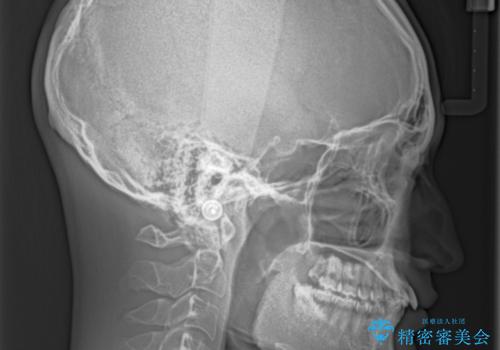

深い咬み合わせとデコボコ ワイヤー矯正で短期治療

インビザラインでの治療も可能でしたが、深い咬み合わせと奥歯の咬み合わせを改善するにあたり、ワイヤー矯正の方が治療期間を短縮できると判断し、ワイヤー矯正をお勧めしました。

結果として、1年かからずに奥歯の咬み合わせを改善することができました。